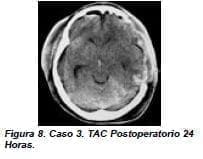

Se le practicó una TAC cerebral (figuras 6, 7) que se mostró hematoma subdural agudo en hemisferio izquierdo, con desviación de línea media, hernia subfalcina y edema cerebral en hemisferio izquierdo. Llevado inmediatamente a cirugía, se le practicó hemicraniectomía izquierda descomprensiva y ventriculostomía para monitoría de la presión intracraneana (figura 8).

En el postoperatorio la presión intracraneana se mantuvo dentro de límites normales por lo que se retiró al cuarto día. Requirió traqueostomía por persistencia de alteraciones de conciencia. Presentó afasia global la cual mejoró en forma progresiva al igual que el estado de conciencia y la hemiparesis derecha. Posteriormente se practicó reposición del colgajo óseo y cierre de la traqueostomía. Fue trasladado a una unidad de cuidado intermedio para continuar su tratamiento de rehabilitación. Tuvo recuperación neurológica.